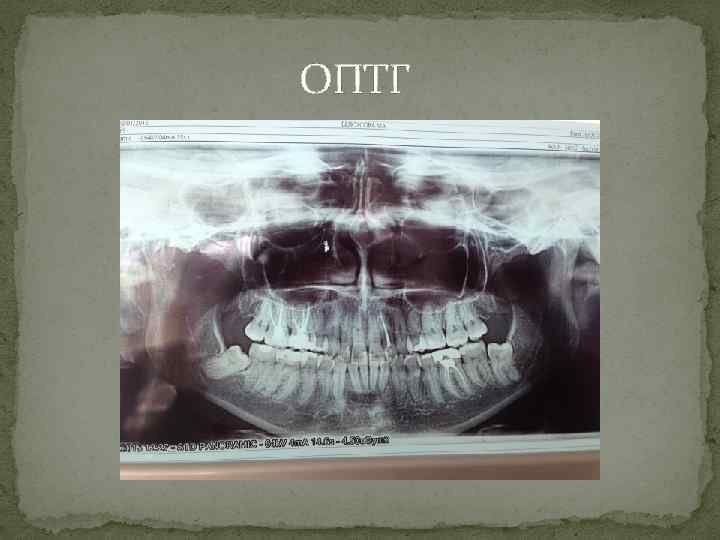

ОПТГ

ОПТГ